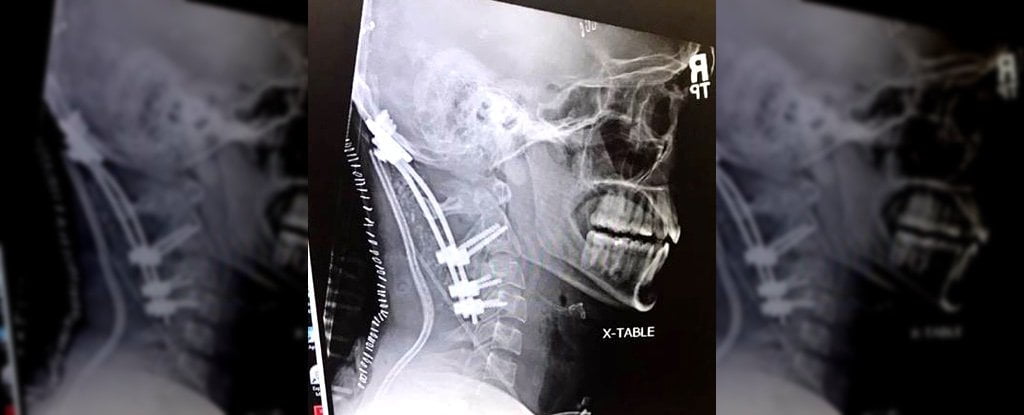

Descobriu-se que Brock havia sofrido uma lesão rara conhecida como luxação atlanto-occipital traumática. Essencialmente – seu crânio se separou de sua espinha.

O neurocirurgião Kashif Shaikh descreveu-o como “quase um evento universalmente fatal”.